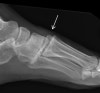

양측 체중부하 상태, 체중부하하지 않은 상태에서 족부 정면 X-ray 사진을 찍습니다.

초기 X-ray에서 정상으로 보여도 통증이 지속되면 재촬영을 실시합니다.

X-ray : Lisfranc 인대 손상 (Lisfranc injury, Midfoot sprain)